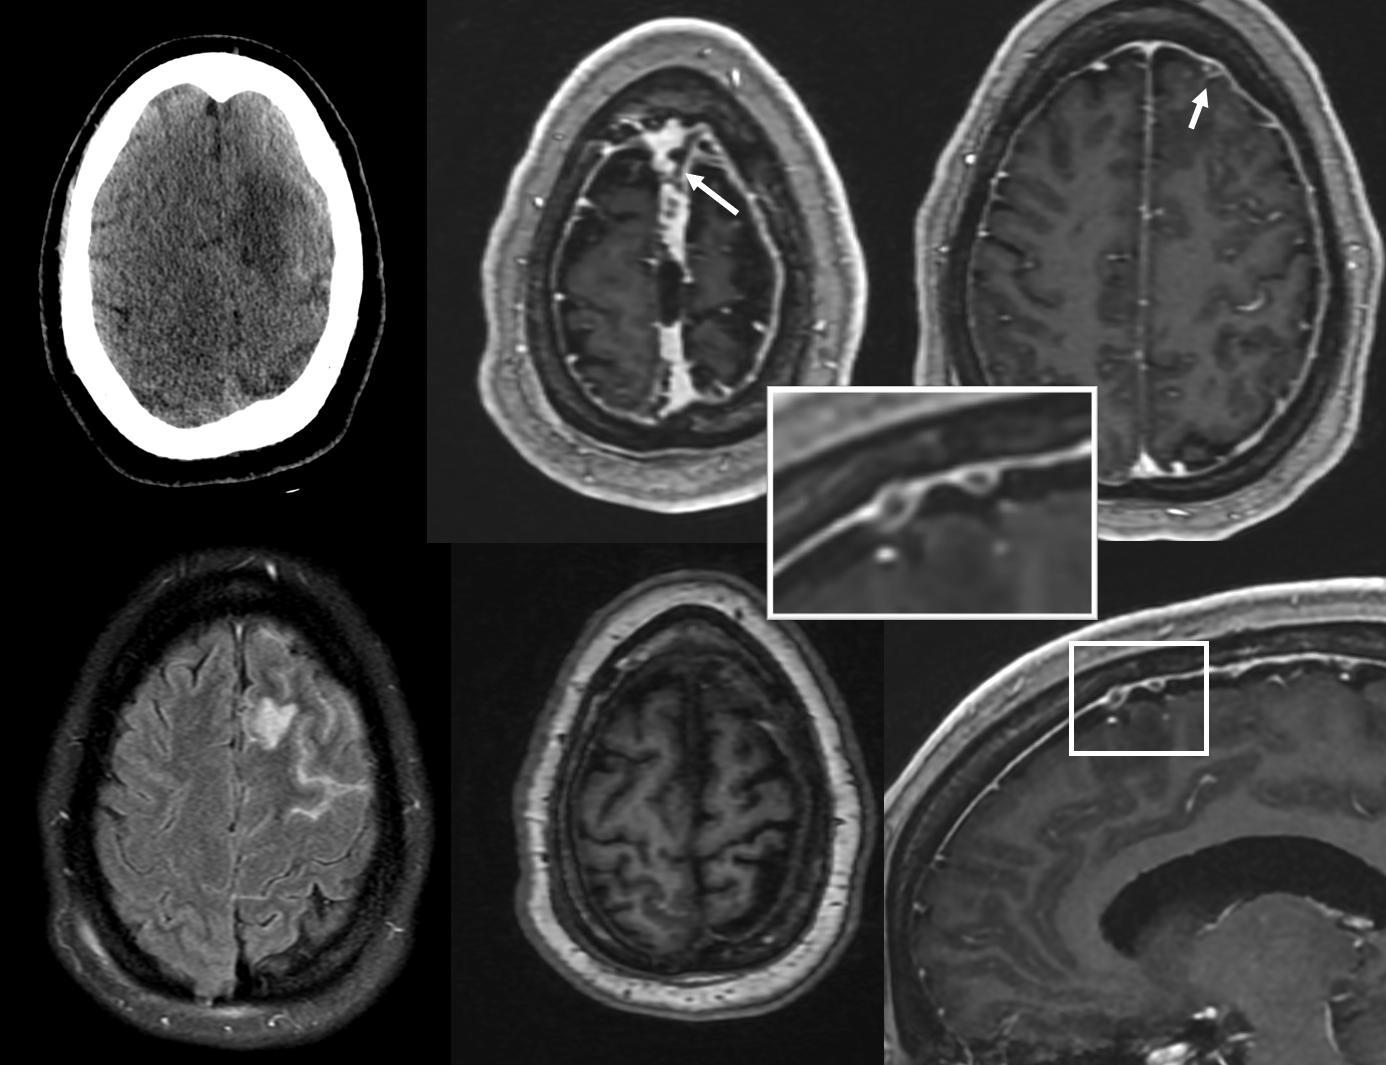

CT/MR — without annotations

With

Treatment with anticoagulation of course